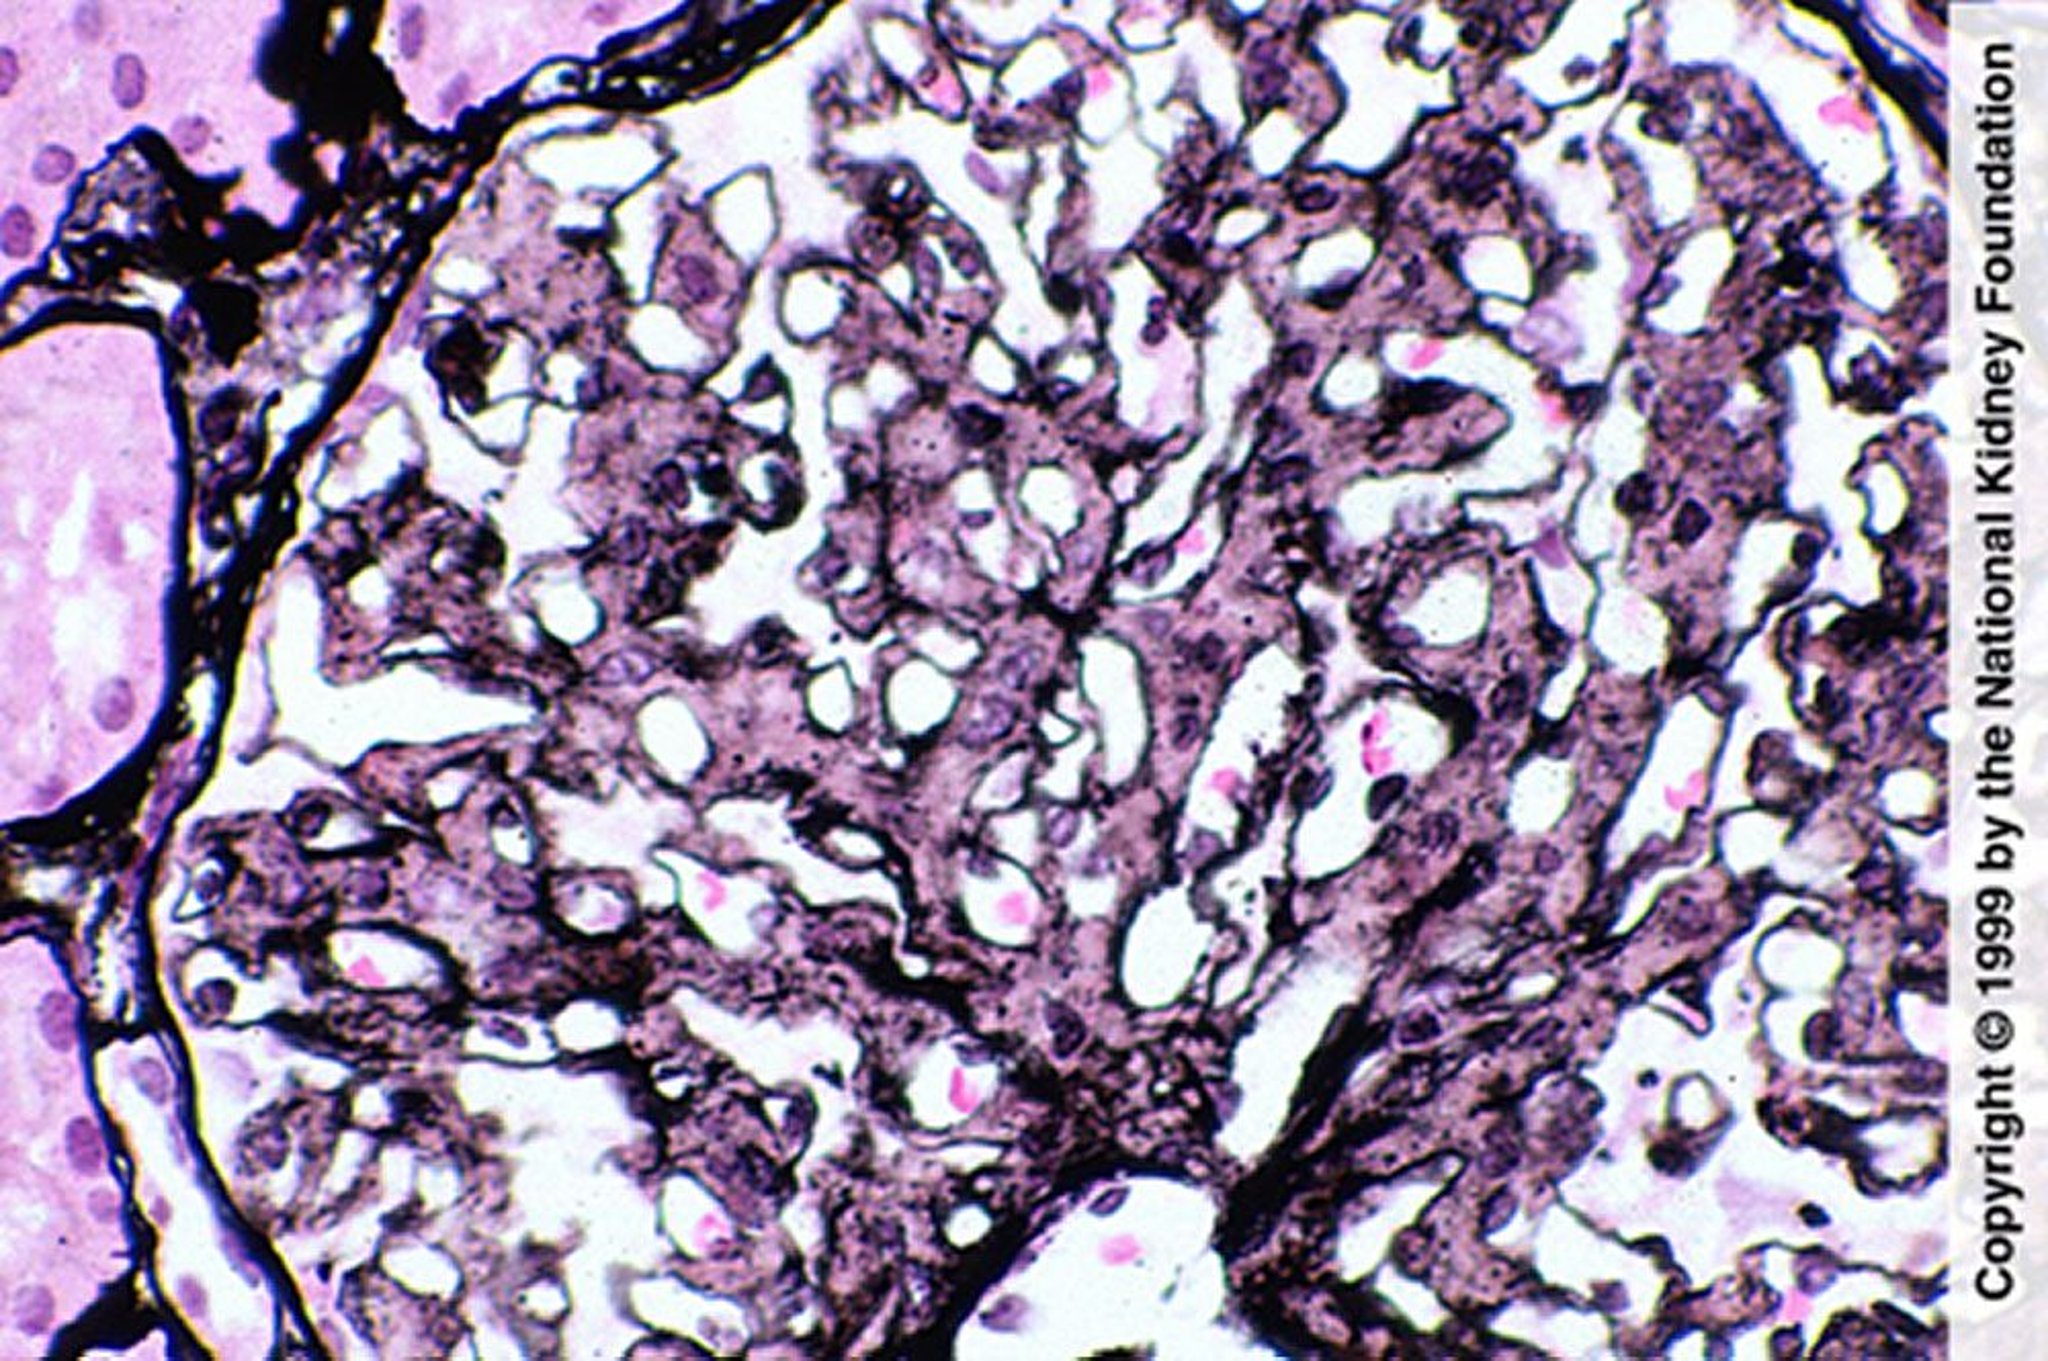

Glomerulopatia fibrilar (proliferação mesangial)

A proliferação mesangial é sugestiva de glomerulopatia fibrilar; mas o diagnóstico requer coloração negativa com vermelho do Congo, imunofluorescência para IgG e demonstração de fibrilas na microscopia eletrônica (coloração prata de Jones, × 400).

Image provided by Agnes Fogo, MD, and the American Journal of Kidney Diseases' Atlas of Renal Pathology (see www.ajkd.org).